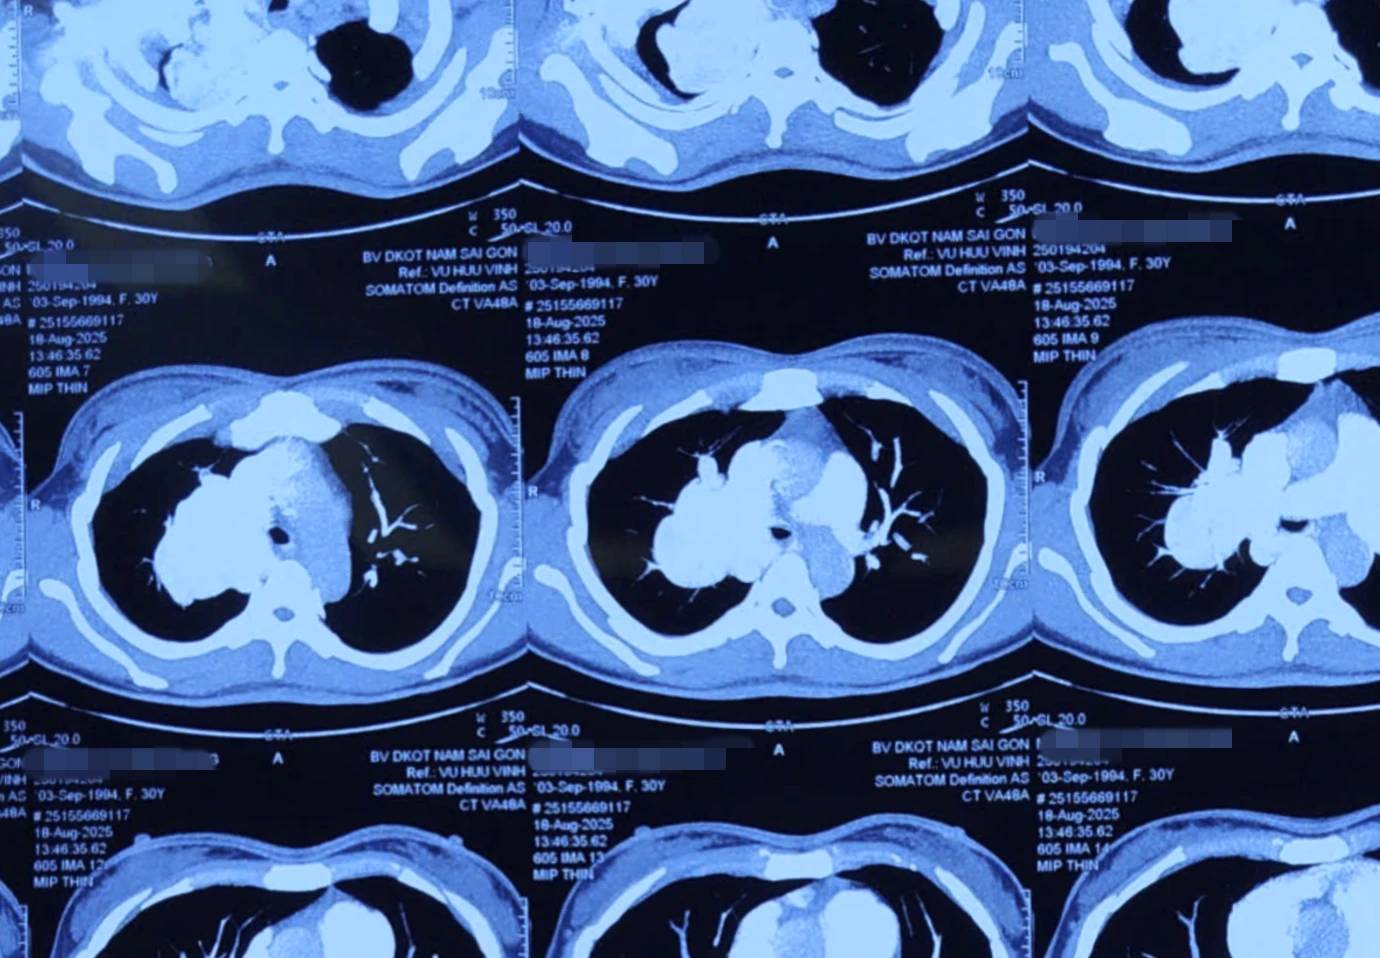

Ngay lập tức, các bác sĩ khoa Ngoại lồng ngực đã cho người bệnh chụp X-quang và MSCT lồng ngực (chụp cắt lớp vi tính đa dãy vùng ngực) để chẩn đoán , phát hiện một khối phình động mạch phổi khổng lồ kích thước khoảng 7cm tại thùy trên phổi phải.

Khối phình này khiến tĩnh mạch phổi trên bên phải giãn tới 2,6cm cùng nhiều bất thường mạch máu khác.

Bệnh nhân mang khối phình động mạch phổi khổng lồ kích thước khoảng 7cm (Ảnh: BV).